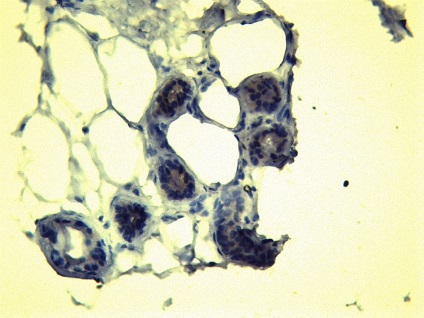

Ábra. 8.9 10 diák a bőr

Ábra. Immunhisztokémia 11: CD-31 expressziója a vaszkuláris endotéliumon, a bőrben a haemangiomatosis

Következtetés (patológus MD Karev VE): egy jóindulatú daganat tömegének faggyúmirigy; haemangiomatosis bőrben, cutan vasculitis (gyulladásos elváltozások érfalak).